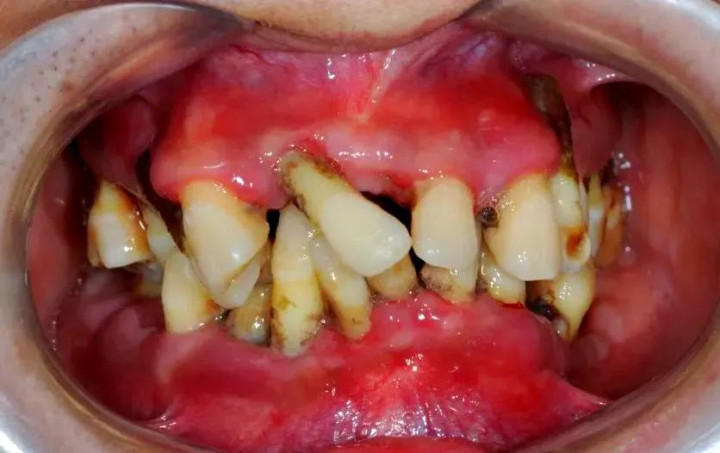

龋齿蛀得太深,细菌如故侵蚀到牙床,大致牙冠基本烂光,补牙、根管调理、牙套都无法支持。这种牙留着不仅没用,还可能成为“细菌窝”,激勉感染。

牙周病是牙齿的“隐形杀手”。当牙槽骨被炎症给与殆尽,牙齿松动得像风中的树叶,无法保留时。